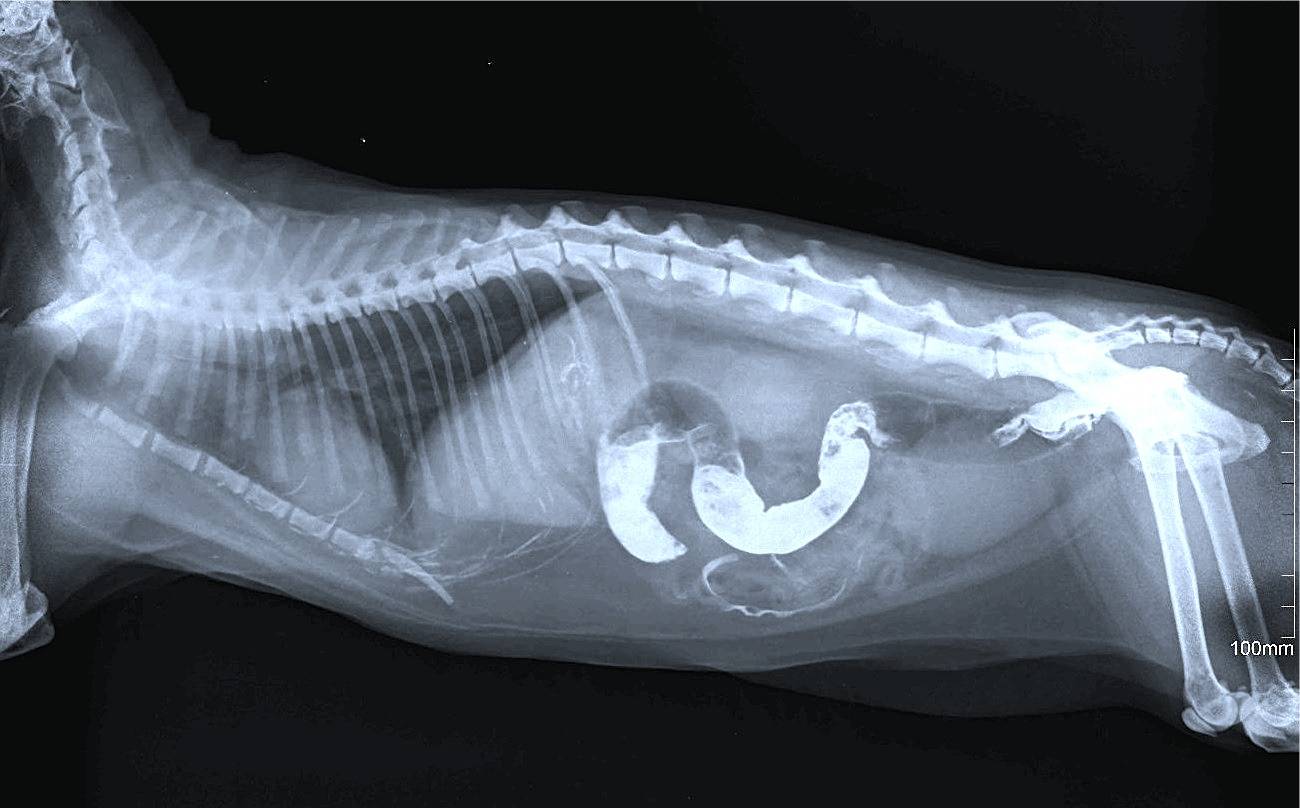

Для диагностики кошке делают рентген с контрастом

- Рентген с контрастом. В качестве контраста используется сульфат бария. С его помощью можно увидеть путь следования пищевого комка по желудку. Кроме того, нередки случаи, когда барий «обволакивал» инородное тело и выводил его с фекалиями. В этих случаях операции удается избежать.

Необходимость визита в ветеринарную клинику не подлежит обсуждению, ведь только здесь есть всё, чтобы поставить точный диагноз и начать лечение животного. Основа постановки диагноза при подозрении на кишечную непроходимость у кошек это — опрос владельцев, тщательный осмотр животного, биохимический анализ крови, чтобы оценить состояние животного и выявить возможные заболевания, рентген с контрастным веществом (сернокислый барий), чтобы создать разницу в плотности тканей и инородным телом для лучшей видимости.